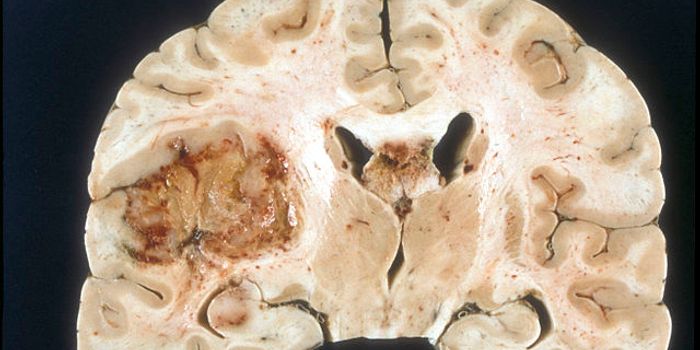

JUL 01, 2016CancerThe diagnosis of glioblastoma often bears one of the grimmest prognosis for patients. But a new research discovery may o ...

MAR 23, 2016CancerIn a large drug screening trial, scientists identified a unique drug combination that is effective against the most aggr ...

MAR 03, 2016Cell & Molecular BiologyFor the first time, scientists have turned skin cells into cancer-hunting stem cells that destroy brain tumors known as ...

DEC 17, 2015NeuroscienceGlioblastomas or GBMs are the most devastating kind of cancer tumor found in the central nervous system in adults. Tumor ...

OCT 22, 2015NeuroscienceWhile any surgery that aims to remove cancerous tumors is risky, there is an increased amount of risk and caution when i ...

JUL 22, 2015NeuroscienceTreating an aggressive brain tumor may have come one step closer to reality recently as a company developing a novel the ...

APR 27, 2015NeuroscienceDeadly brain tumors called high-grade gliomas grow with the help of nerve activity in the cerebral cortex, according to ...